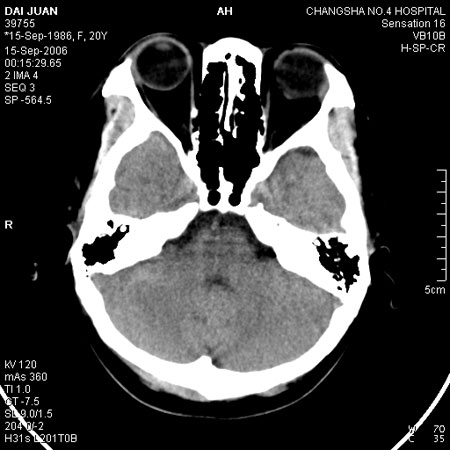

请问各位战友:图示箭头处是否为颅骨骨折?

病史:患者,女,20岁.头部及腹部外伤20分钟.伤后昏迷,无呕吐.头及右侧腰背部疼痛,双侧瞳孔等大,

右肾区叩痛.其它无异常.患者家属否认原有外伤史.

请大家看看是否为颅骨骨折.还是正常变异,或为陈旧骨折.谢谢.

图片未上传完,所见图象示枕骨线样低密度影,边缘锐利,结合外伤史,伤后昏迷,骨折不能除外。

枕骨的线样低密度影锐利、清晰,但正好位于矢状缝的位置,局部无明显软组织肿块,相临及对冲部位脑实质亦无出血及挫裂伤表现。

单就这几层暂不考虑骨折,建议上传完整图片。

楼主所关心的另一个线样影应该是头颅矢状面略偏左,射线正好穿过所致,不需要考虑骨折。

枕部锐利透亮线,可以考虑枕骨骨折.

枕骨是单块的,矢状缝是在顶骨而不是在枕骨,枕骨后缘见线状低密度,边缘税利,考虑在骨折存在。

枕后部及左侧颞枕部边缘锐利的线样低密度影,局部软组织无异常,左侧乳突蜂房密度均匀,硬膜下及脑实质内未见出血灶,考虑为正常变异。

枕部锐利透亮线,可以考虑枕骨骨折.左侧枕颞缝。

枕部考虑骨折。一般的颅逢不会跨越板障,楼主所示枕骨断面两侧板障也不连续。

需注意软组织改变和皮质是否存在,如果皮质存在,线影锐利,既使局部外伤,亦不应诊为骨折,请酌!

另外,本例扫描体位不正,亦为影响判断之重要因素如颞枕缝!